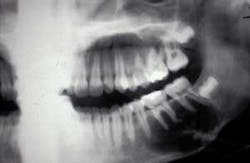

The related radiograph depicts a radiolucent lesion around the mandibular molar teeth extending from the second premolar to the distal of the second molar. The border of the radiolucent lesion may be described as scalloped and reaching to the inferior border of the mandible. The scalloping in between the roots follows the nature of the traumatic bone cyst.

Diagnosis: Traumatic bone cyst